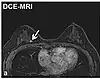

Dynamic contrast enhancedDCEMeasures changes over time in the shortening of the spin–lattice relaxation (T1) induced by a gadolinium contrast bolus.[88] Faster Gd contrast uptake along with other features is suggestive of malignancy (pictured).[89]